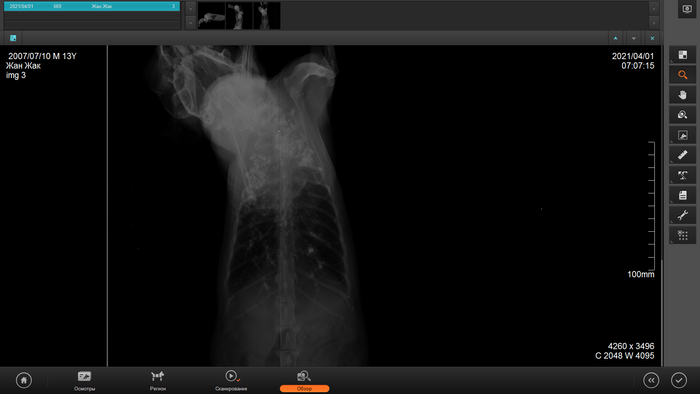

Это рентген за сеоодняшний день,здесь уже чётко видно новообразование, у кота начались приступы,задыхается.